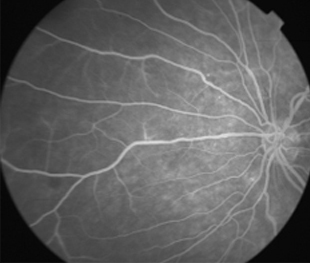

Angiografía OI

IDX

Retinopatía de Purtcher Secundaria a Embolismo Graso después de Liposucción

- Angiografía: teñido arterial, escape capilar, más tardíamente, no perfusion arteriolar y venular con teñido de las paredes vasculares y dilatación venosa.